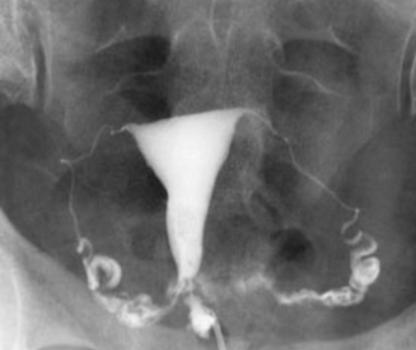

HSG

HSG Hysterosalpingography, also known as uterosalpingography, is a radiologic procedure to investigate the shape of the uterine cavity and the shape and patency of the fallopian tubes. This means it is a special x-ray using dye to look at the womb and Fallopian tubes.